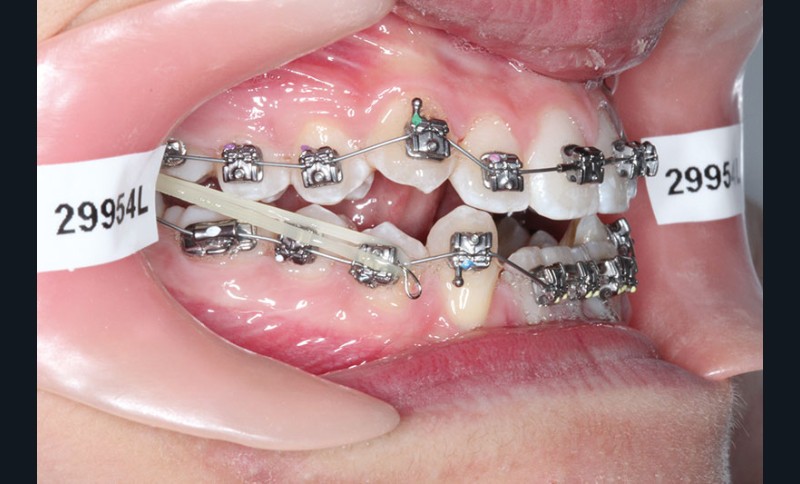

2e phase : mise en place du système multibague Carriere SLX (fig. 7 à 9)

Nous continuons le port des élastiques…